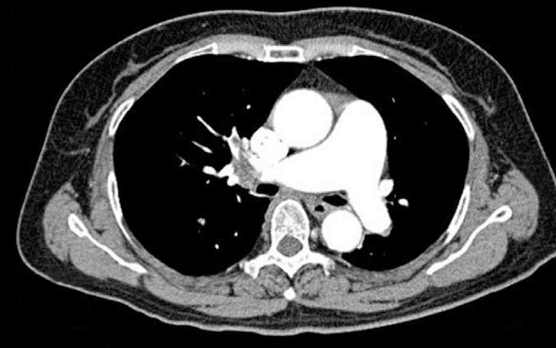

CT: Rt. pulmonary a. thrombosis

Chest CT상 폐동맥 혈전이 저명하게 관찰되므로 호흡곤란의 원인을 폐색전증으로 진단할 수 있다.